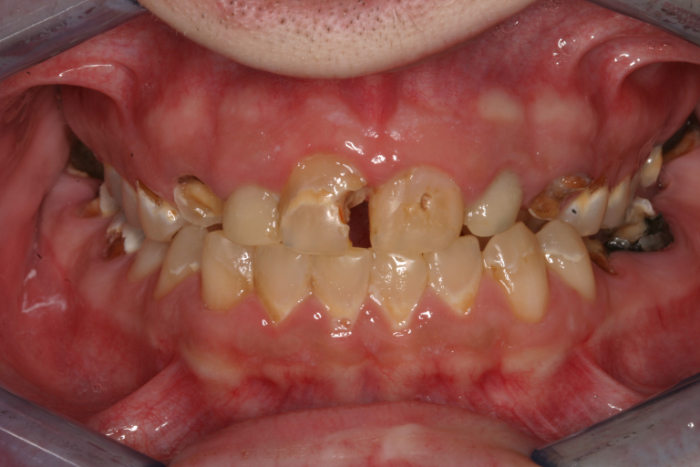

For example, one patient of a general dental practice had a caries-free history for 35 years. He ceased smoking traditional cigarettes and decided to vape as he thought this was a healthier alternative. Within a year, cervical enamel demineralization and interproximal lesions were present on the mandibular anterior sextant, consistent with the primary point of contact of the e-liquid aerosol (figure 2).

Figure 2: Effects of e-cigarette usage